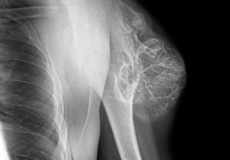

Multiple Hereditary Exostosis (Osteochondromas)

Multiple hereditary exostoses is a rare genetic condition in which an individual develops multiple bone tumors called osteochondromas, often on the growing ends of long bones or on the hips or shoulder blades. These tumors are non-cancerous but can cause growth problems in the affected bones.